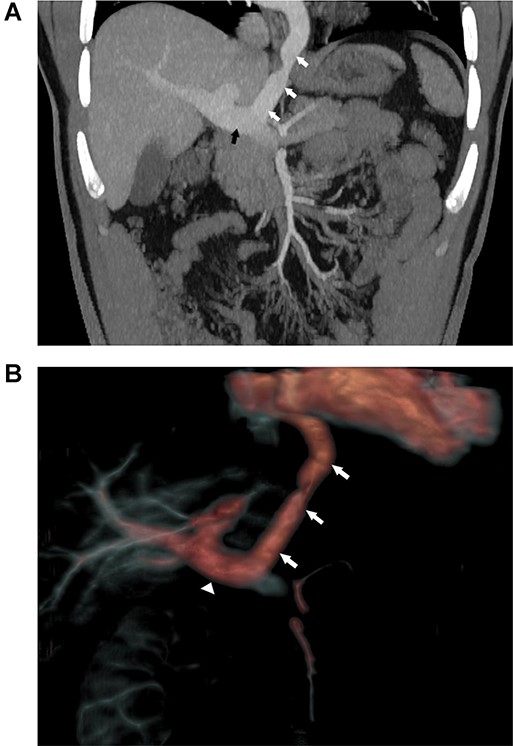

Surveillance MRI was performed together with exercise testing at 25 years of age and excluded any focal pulmonary vein stenosis. The right ventricle was dilated, but with preserved systolic function (EF = 49%) and the portal vein, connected with the LA and the common pulmonary vein confluence, which was dilated. A triple-phase computed tomography (CT) scan (Fig. 1A) demonstrated a large vessel connecting the postero-inferior aspect of the LA and the mid-point of the portal vein. A CT scan with 3D reconstruction was performed to further clarify the anatomy (Fig. 1B).

(A) Coronal view of abdominal CT with contrast demonstrating the large vessel (white arrows) between LA and portal vein (black arrow). (B) 3D reconstruction of CT with contrast demonstrating the large vessel (arrows) between LA and portal vein (triangle).